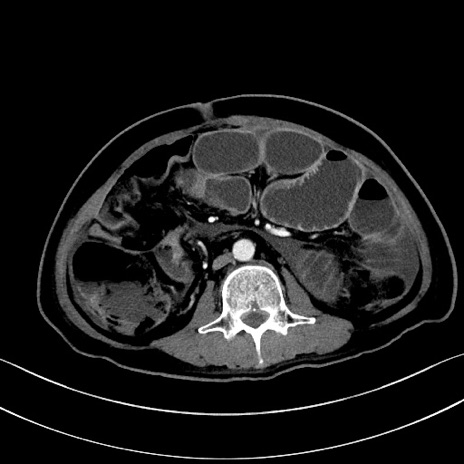

冠状断像

【症例】60歳代男性

【主訴】嘔吐

【現病歴】胃癌にて胃全摘後。食思不振が悪化し、夜中に嘔吐することがある。

【既往歴】胃癌、胃全摘、脾摘、胆摘後

【データ】WBC 5900、CRP 10.56